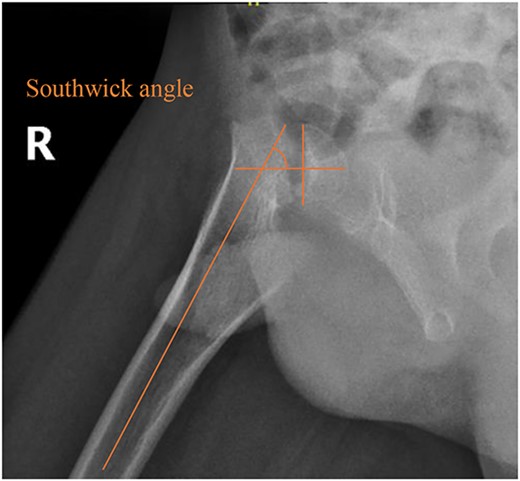

A 5-year-old independent ambulatory Middle Eastern boy with CP who was born preterm and developed grade III intraventricular haemorrhage and periventricular leucomalacia and was on AEDs, including valproic acid (VPA) and levetiracetam (LEV), for >3 years and was controlled over the last year (no history of seizure attack) presented to the emergency room (ER) with right hip pain and inability to bear weight for 4 weeks; the patient had no history of fever or trauma. Physical examination shows a thin, the weight is 12 kg, the height is 101 cm, vital signs within the normal range, tenderness over the right hip, and external rotation of the right hip, with restricted hip mobility. A radiological study was performed ~3 months before the patient presented to the ER for follow-up examination of a left hip coxa valgus deformity with no apparent abnormalities in the right hip (Fig. 1). Initial imaging studies conducted in the ER showed an anterior–posterior view of the pelvic radiograph, revealing Klein’s line [13] not intersecting the capital femoral epiphysis (Fig. 2), and frog-leg lateral view radiograph of the right hip (Fig. 3) confirmed SCFE and Southwick’s slip angle [13] of ~50° (moderate). Laboratory findings were clear for endocrine and renal diseases or infection, except for low vitamin D (total 25-OH Vitamin D: 43.4 nmol/L), suggesting vitamin D insufficiency. The diagnosis was confirmed with clinical and radiological studies as right-sided unstable SCFE requiring surgery. Surgical intervention was performed with percutaneous in situ fixation using a single fully threaded 4.5-mm cannulated screw (Fig. 4). Postsurgical rehabilitation included non-weight-bearing right lower extremities for 6 weeks. Regular follow-up with serial radiology studies showed stable fixation with no migration of screw or further slippage at 6 weeks (Fig. 5) and 3 (Fig. 6), 15 (Fig. 7), and 36 months (Fig. 8). During follow-up, a painless range of motion in the right hip was observed, with full weight-bearing and resumption of his usual activities with no complaints.

Pelvic frog-leg lateral view radiograph showing Southwick’s slip angle 50° in the right hip.